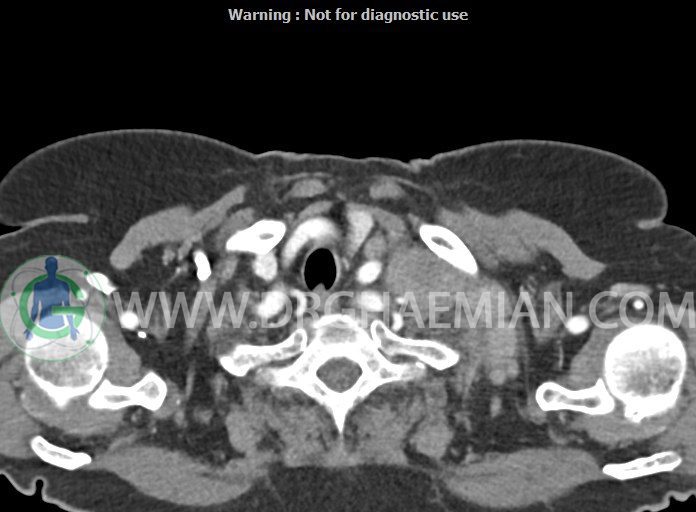

در سی تی اسکن اسپیرال از گردن با تزریق (مولتی دیدکتور 16 با مقاطع ظریف و بازسازی های ساژیتال و کرونال):

– تصویر توه های نسج نرمی oval shape متعدد با Enhancement تقریباً هوموژن، قرار گرفته در سمت چپ گردن، در لول غضروف کریکوئید با اثر فشاری شدید و compression ورید ژوگولار، با گسترش تحتانی به اینفراکلاویکولار چپ، به حداکثر ابعاد 28x50mm (با Enhancement مختصر هتروژن در این توده)

در درجه اول مطرح کننده لنفادنوپاتی متاستاتیک مطرح می باشد بالین، تومورهای منشأ گرفته از غلاف عصبی زنحیره سمپاتیک چپ گردنی، شبکه براکیال و لنفوم نیز در DDX قرار دارند. لذا نمونه برداری بافتی جهت بررسی بیشتر توصیه می شود.

– اسکولیوز مهره های سرویکال با تحدب به راست، احتمالاً در زمینه اثر فشاری توده های مذکور

مشهود است.